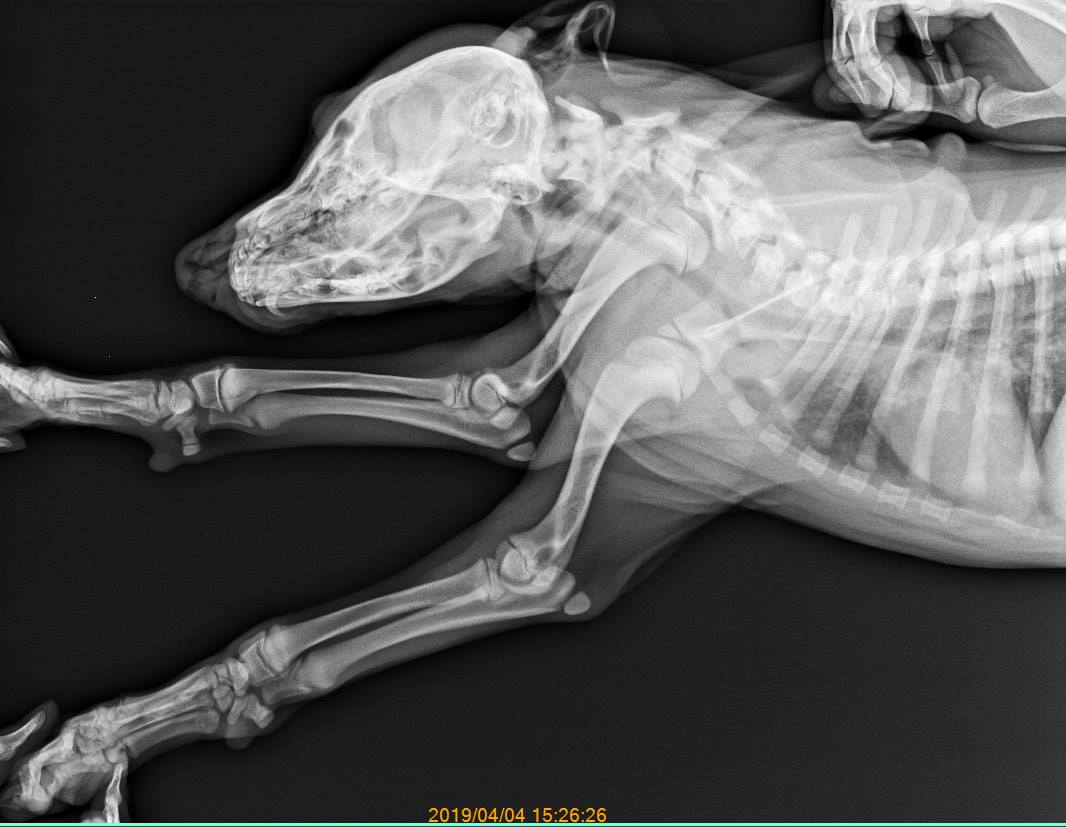

而動保人士徐文良在看到影片後馬上連絡學生,表示為了避免狗狗再度身陷危險處境,願意接手遭踹的狗狗以及與牠同一窩共6隻約3個月大的幼犬,徐文良因為擔心受虐幼犬的傷勢,於是先送至嘉義培安動物醫院進行健康檢查,所幸狗狗身上並無明顯外傷,X光檢查也沒有骨折、錯位等症狀,只不過有貧血的現象,而且徐文良也強調,狗狗因為頻頻地發抖明顯是受到驚嚇,希望可以早日被認養,在安穩的環境下讓牠能忘記恐懼。